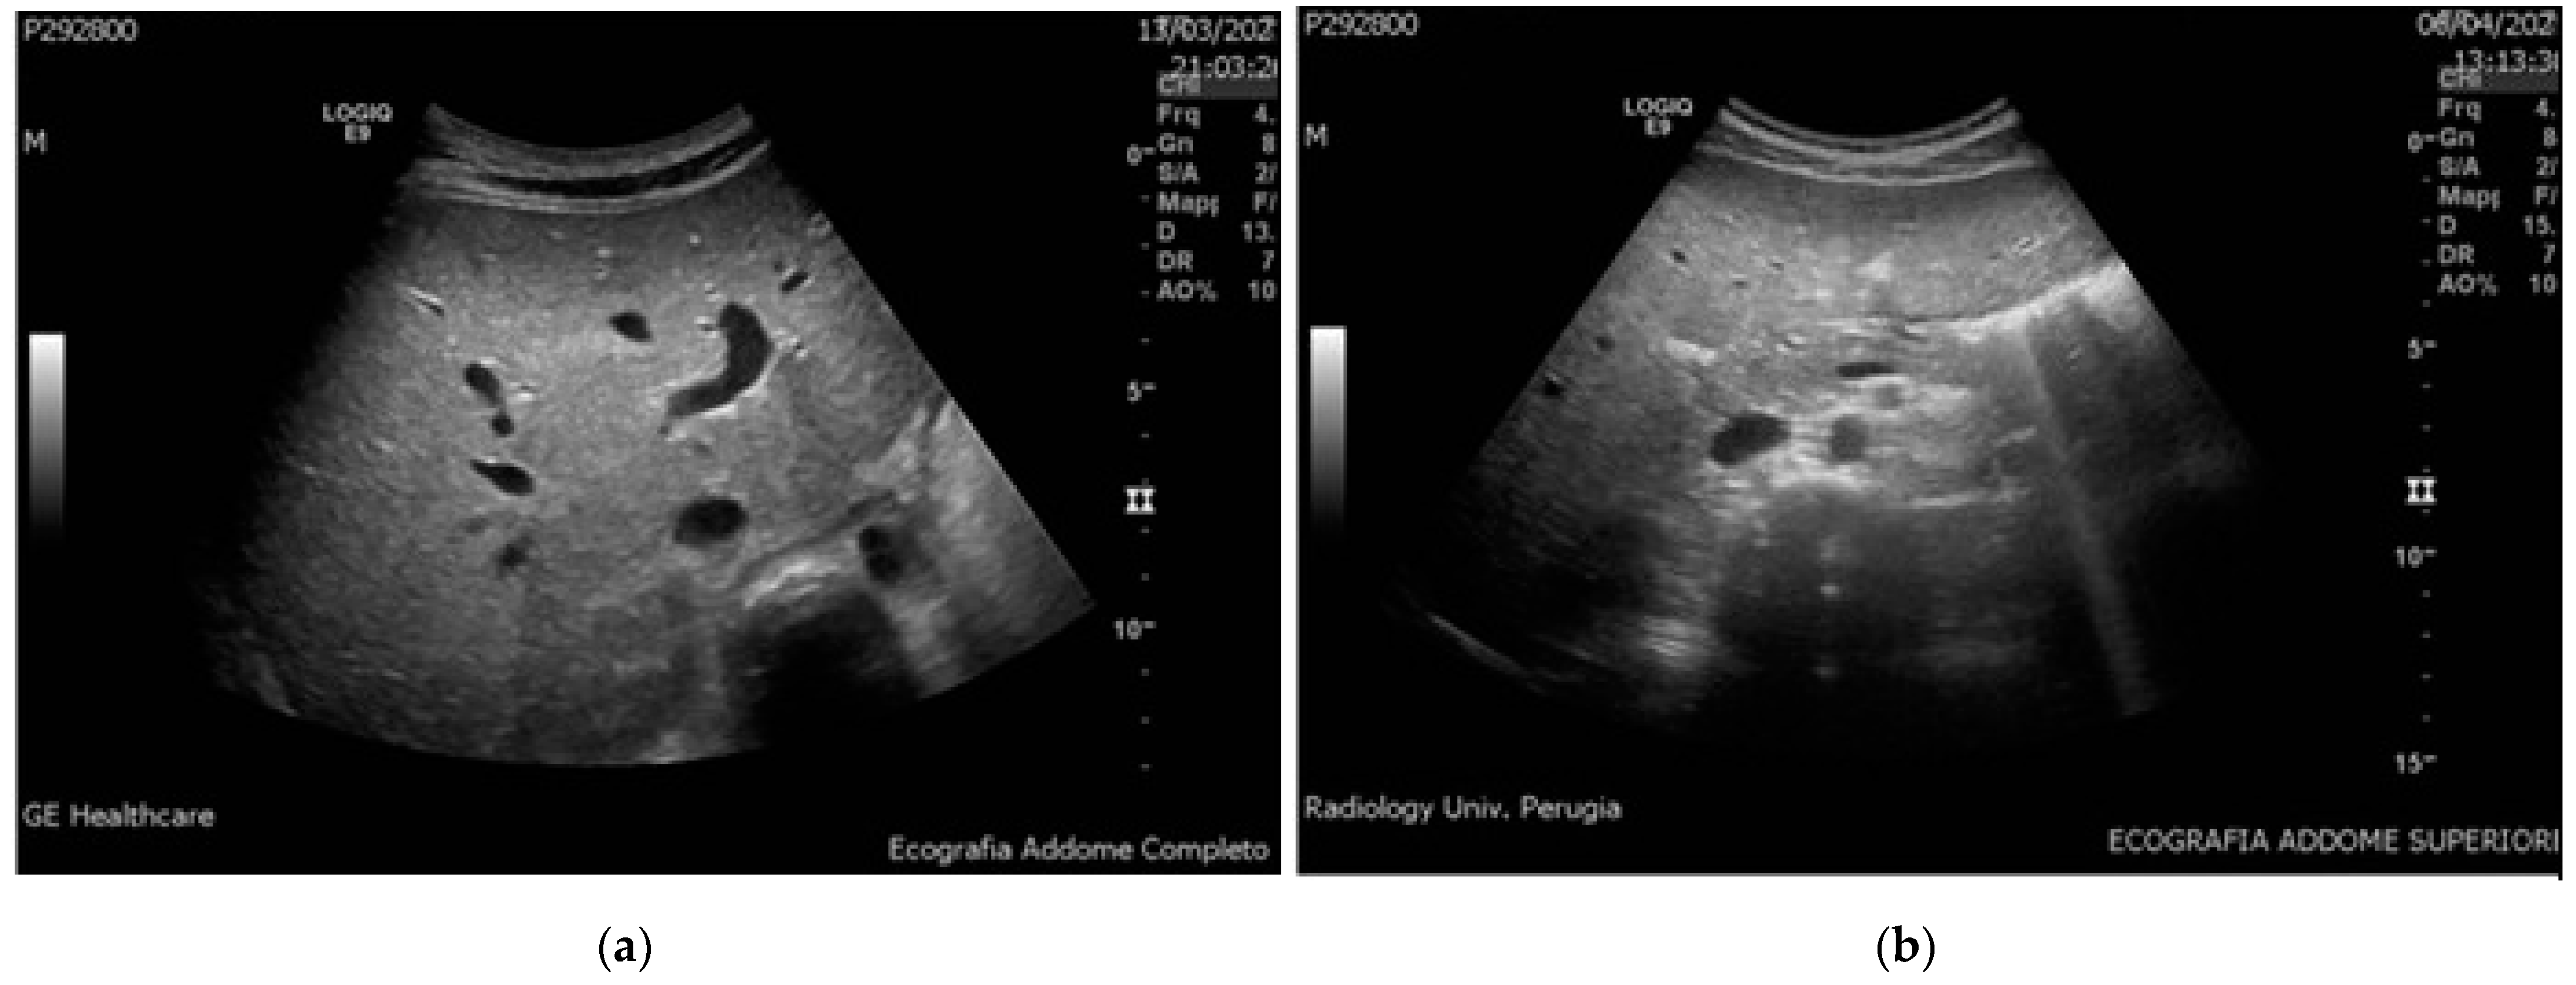

New Onset of Hepatic Steatosis Post-Severe Multisystem Inflammatory Syndrome in Children (MIS-C): A Case Report

2. Case Report